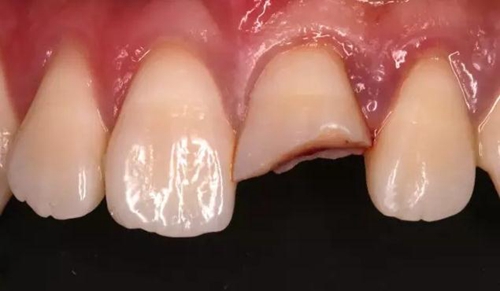

口內(nèi)檢查:21切1/3-1/2折斷,髓腔暴露,探痛明顯

近中鄰面探及齲損,松-,叩+,齦緣輕度紅腫,探及齦下結(jié)石。

術(shù)前口內(nèi)照

斷冠

折斷之牙體嚴(yán)重脫水,呈白堊色,斷端對(duì)位后吻合度較好,僅少許牙體缺損。